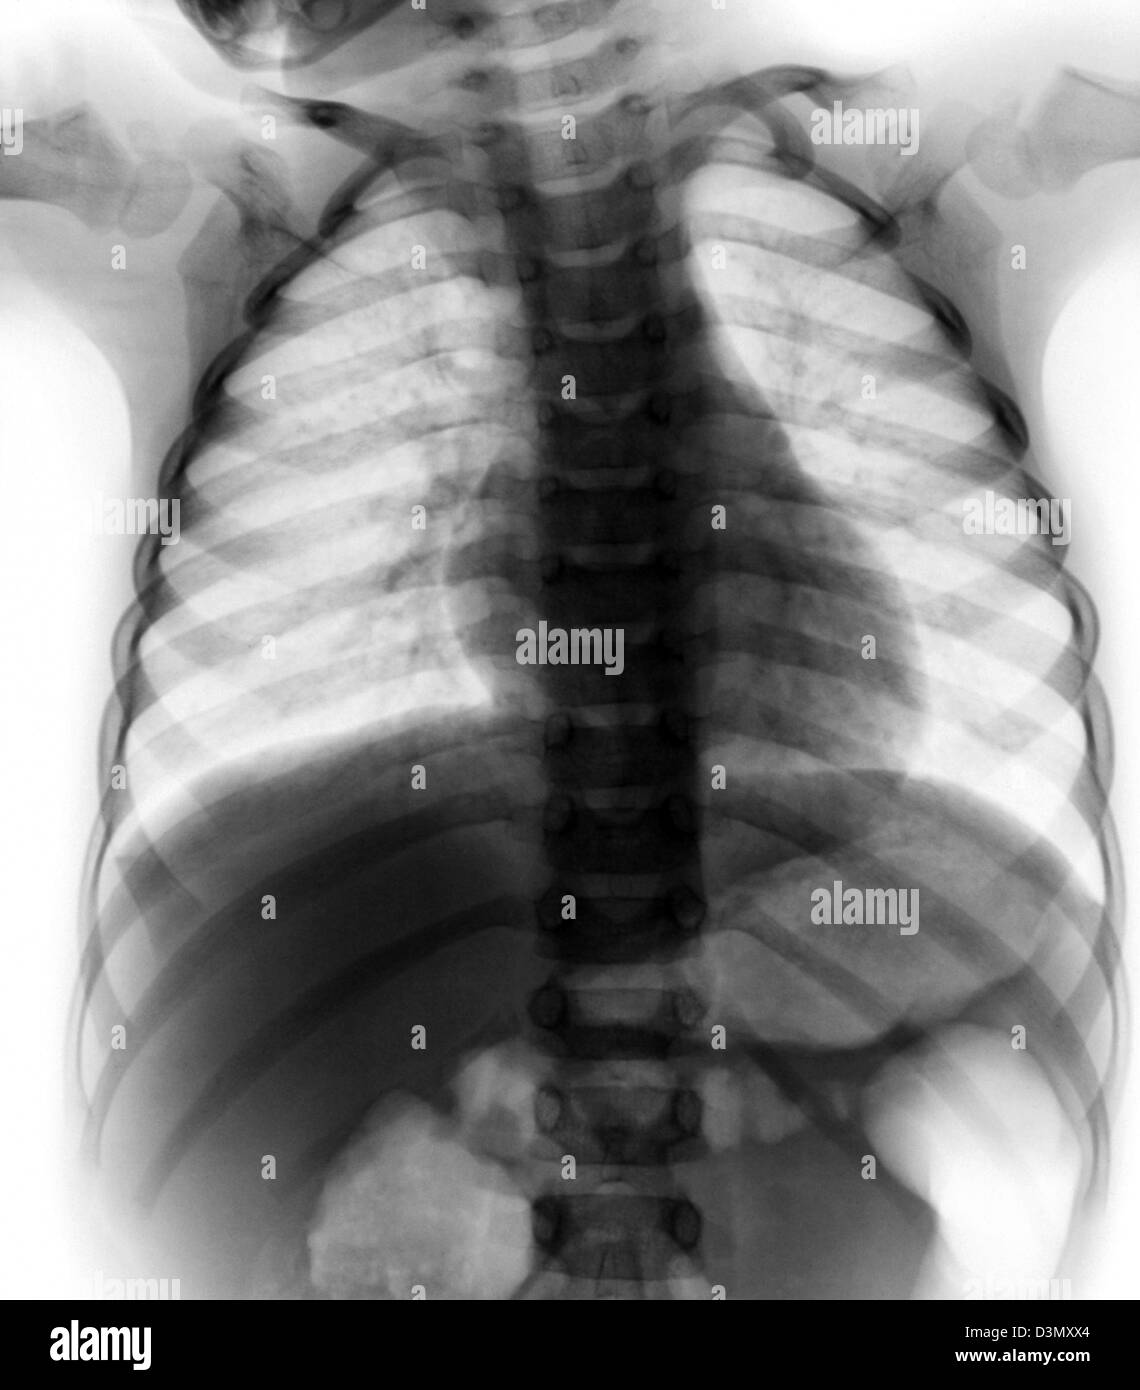

normal chest xray of a 3 year old boy Stock Photo 53935228 Alamy Normal Chest X Ray 3 Year Old this article lists examples of normal imaging of the pediatric patients divided by region, modality, and age. ( 1) the relative size of a lung or hemithorax, ( 2) the degree of. Imaging plays a critical role in elucidation of differential. a collection of blood or fluid around the lung. This can occur with congenital heart disease or. Normal Chest X Ray 3 Year Old.